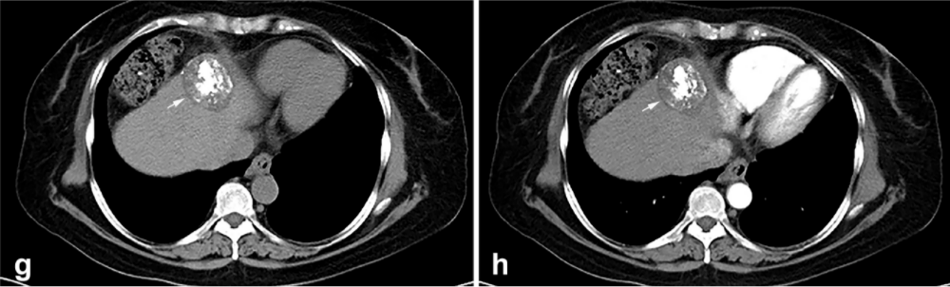

背景:由于一些原因,位于膈肌附近的腫瘤的熱消融在技術(shù)上具有挑戰(zhàn)性。首先,術(shù)中計(jì)算機(jī)掃描和超聲檢查無(wú)法清晰顯示射頻消融/微波消融切緣。第二,消融過程中不利的針分布和過熱可能導(dǎo)致肝包膜破裂,并對(duì)膈、肺和心臟造成嚴(yán)重?fù)p傷。第三,即使使用人工腹水,仍有9~22%的患者因肝周粘連或腫瘤位置靠近肝表面而導(dǎo)致膈肌熱損傷。冷凍消融可能是毗鄰膈肌的HCC的一種有前途的治療方法,因?yàn)樵谙谶^程中使用CT和US可以很好地顯示腫瘤邊緣。盡管一些研究評(píng)估了在高危區(qū)域使用冷凍消融治療HCC,但很少有研究針對(duì)膈肌臨近區(qū)域。

① 術(shù)后 1 月腫瘤治療反應(yīng):冷凍消融術(shù)后一個(gè)月腫瘤疾病控制率達(dá)95.9%。

③ 總生存曲線和局部腫瘤進(jìn)展曲線:冷凍消融后中位生存時(shí)間為 27.3 個(gè)月,中位局部腫瘤進(jìn)展時(shí)間為 20.9 個(gè)月。